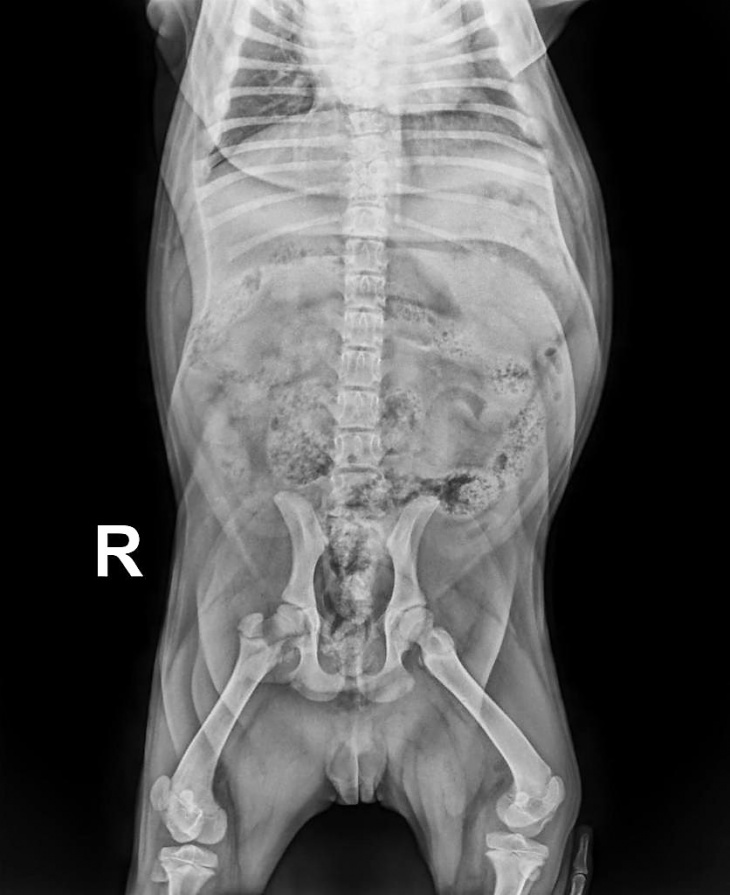

A partir de los tres meses de edad se comenzaron a notar ciertas dificultades para deambular, mostrando una incoordinación a nivel del tren posterior. En la medida que el cachorro fue creciendo, fueron haciéndose más evidentes, por lo que se realizaron radiografías que se adjuntan.

Este caso se diagnosticó como espina bífida cerrada.

La ubicación de la alteración medular a nivel de L7-S1 tiene íntima relación con los síntomas clínicos. La evolución de la sintomatología es coincidente con el diagnóstico.